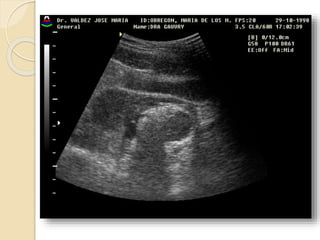

Ecografia tocoginecologica